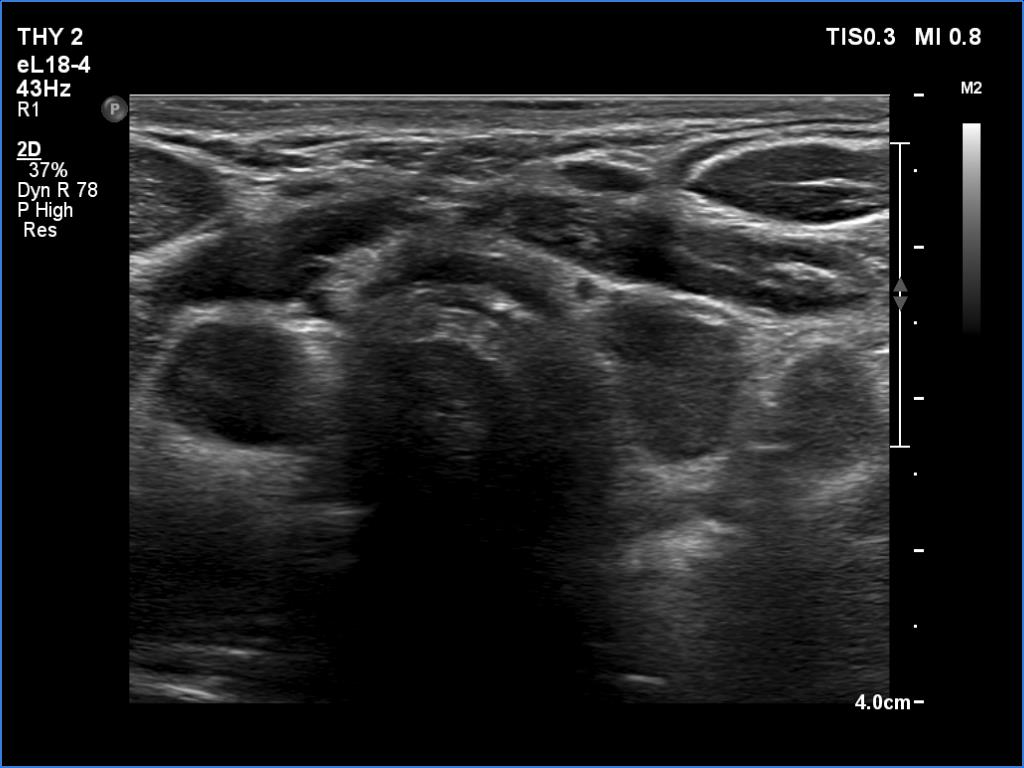

Follow-up examination 8 years later (4th and 5th rows of images):

Clinical data: The patient was referred for evaluation of a continuously increasing thyroglobulin level which resulted in 2.86 ng/mL, 5.74 ng/mL and 20.1 ng/mL, at the 2-yr, 5-yr and 7-yr follow up. Cytology of enlarged lymph nodes, multiple CT-scans and PET-CTs failed to reveal recurrence.

Palpation: There were two palpable, firm but freely moveable masses in the right and left submandibular area.

Hormonal examination: indicated euthyroidism with TSH 2.95 mIU/l on daily 125 microgram levothyroxine. Thyroglobulin was 15.4 ng/mL, anti-hTg was below 20 U/mL.

Ultrasonography revealed hypoechoic discrete lesions in both thyroid lobes. The lesions presented microcalcifications. Corresponding to the palpable mass in the right submandibular region, a reactive-type regular lymph node was found. There was an enlarged lymph node in the left submandibular region. The node had a regular hilum but displayed a heterogeneous pattern.